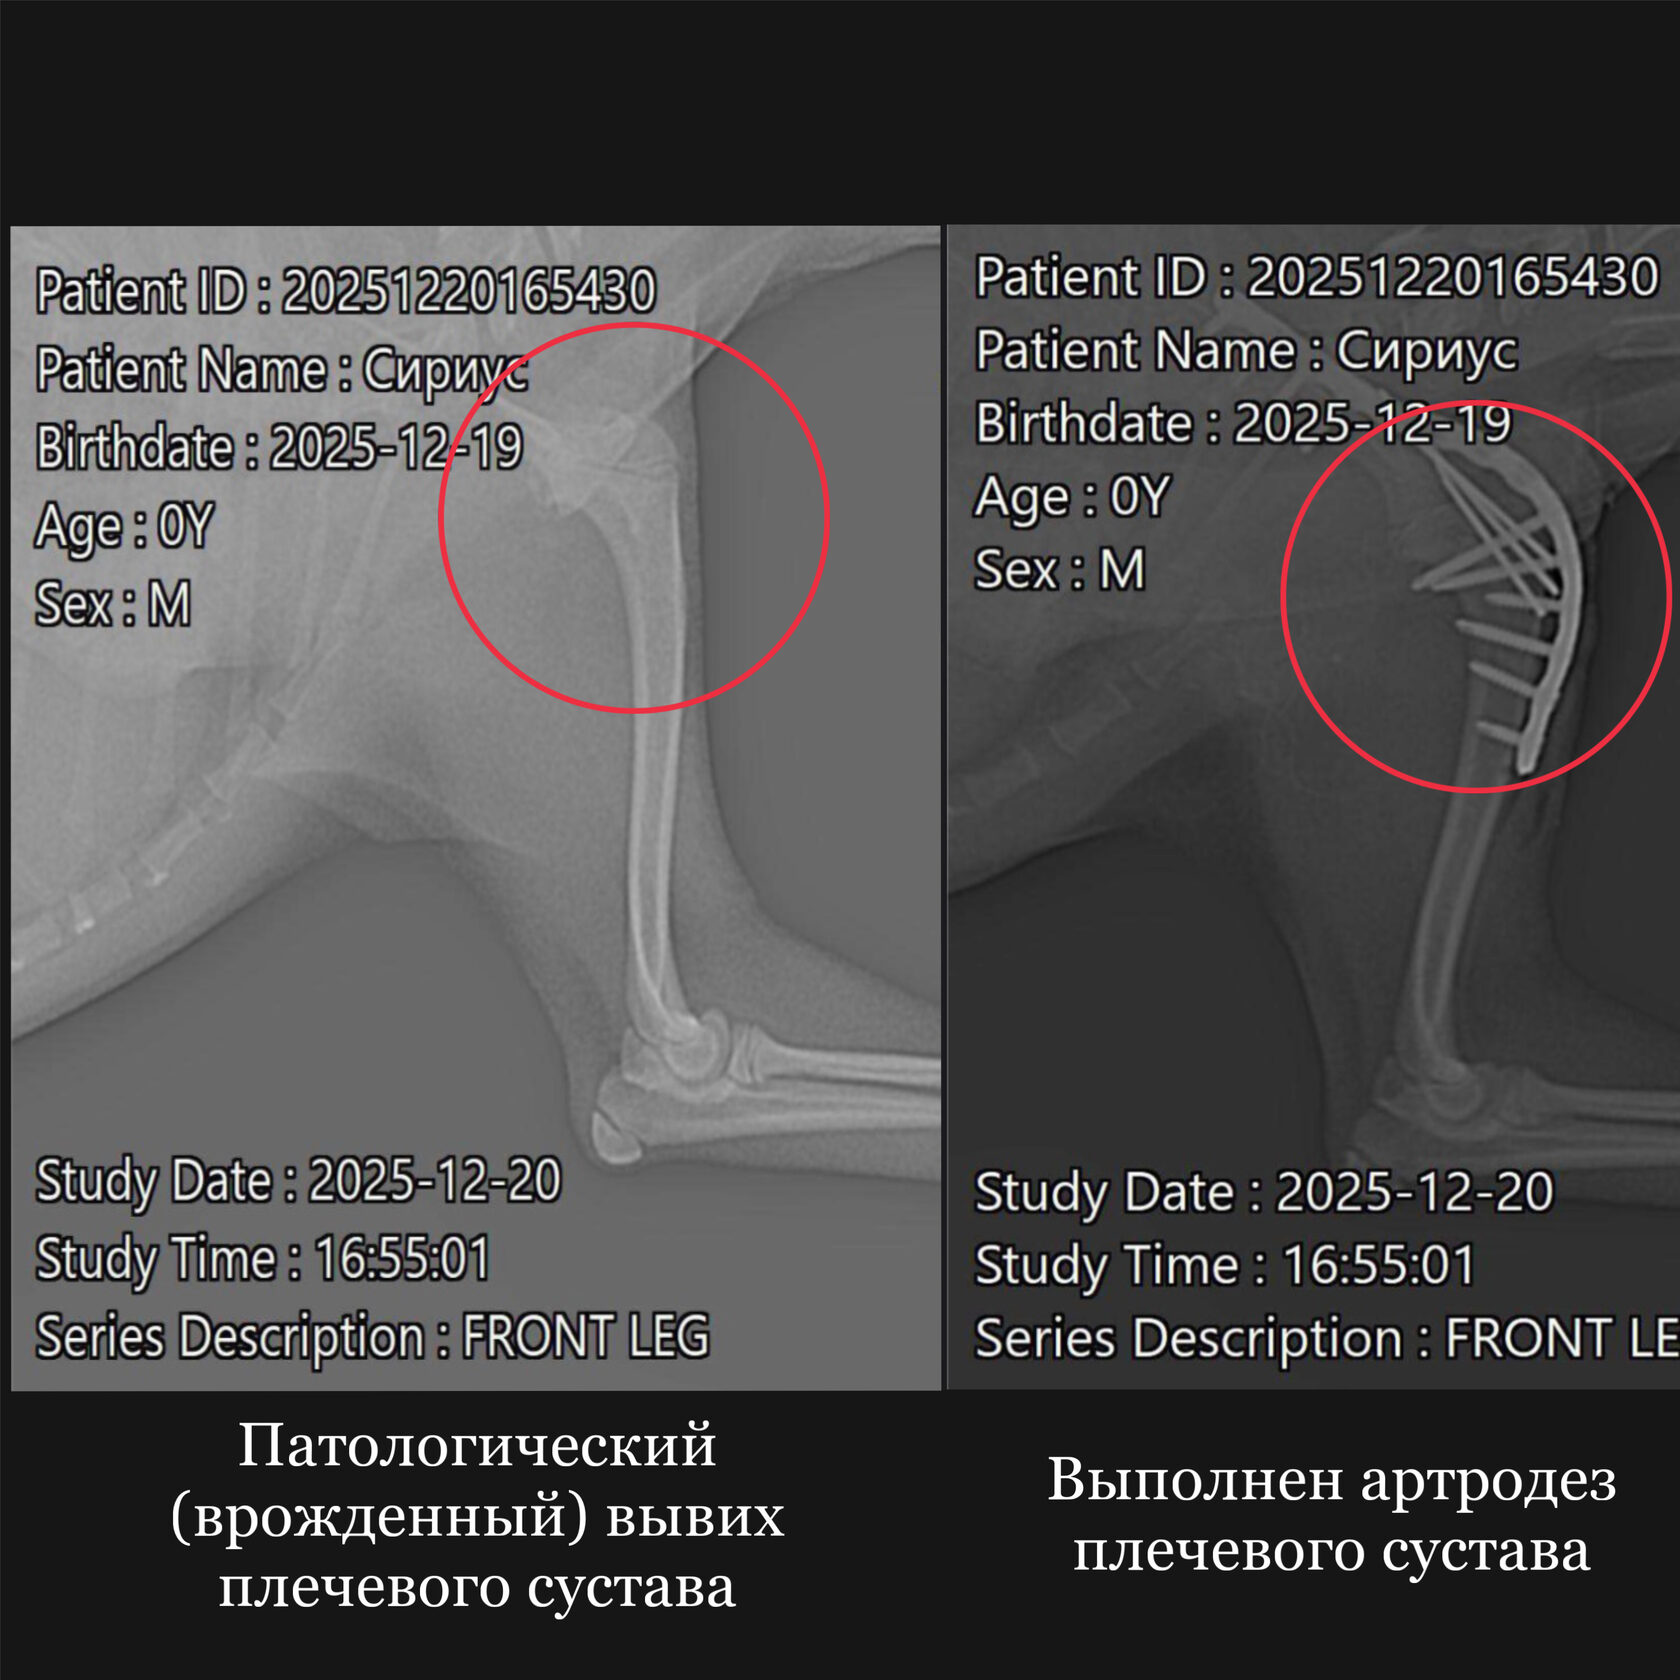

Ветеринарная травматология охватывает широкий спектр состояний: от вывихов и растяжений до сложных переломов. Ветеринар-травматолог применяет как консервативные методы (иммобилизация, медикаменты, физиотерапия), так и хирургическое вмешательство.

При сложных повреждениях используются остеосинтез, артроскопия и другие современные техники. Лечение проходит под контролем врача-анестезиолога, с учётом возраста и состояния животного.